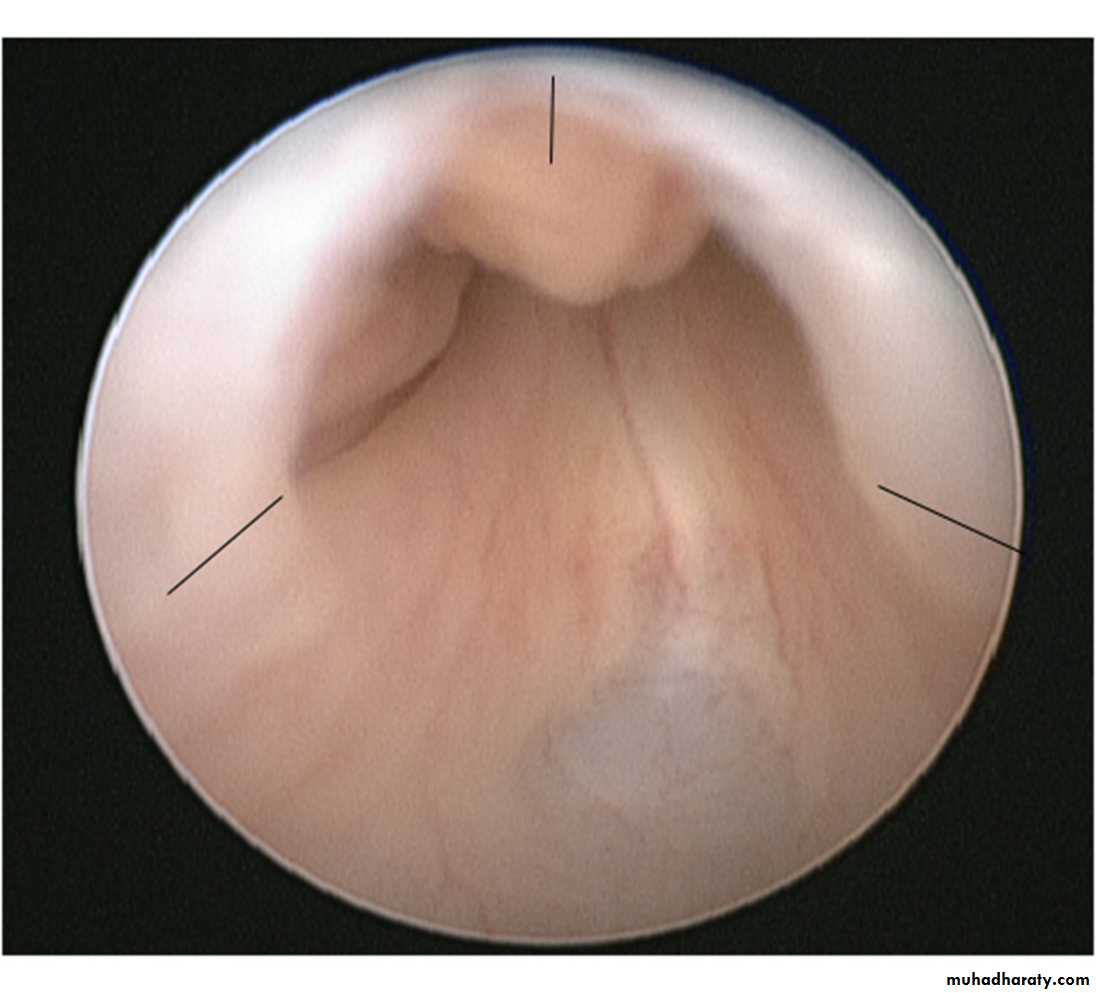

Posterior urethral valves (PUV) are abnormal congenital mucosal folds in the prostatic (posterior) urethra causing lower urinary tract obstruction.

Classification

Type I (90–95%): Membranes arise from the distal lateral aspect of the verumontanum,1 which extend distally and anteriorly to fuse in the midline.

Type II: Longitudinal folds extending from the verumontanum to bladder neck .

Type III (5%): A ring-like membrane found distal to the verumontanum

EtiologyNormal male urethra has small, paired lateral folds found between the lateral, distal edge of verumontanum and lateral urethral wall.

PUVs probably represent a congenital overgrowth of these folds from abnormal insertion of Wolffi an ducts into the posterior urethra during fetal development.